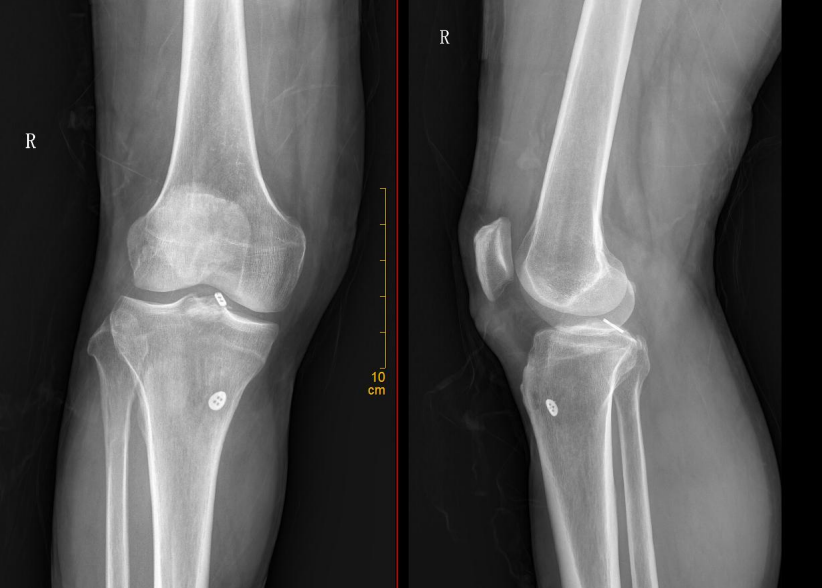

术后X线片

分型及术式